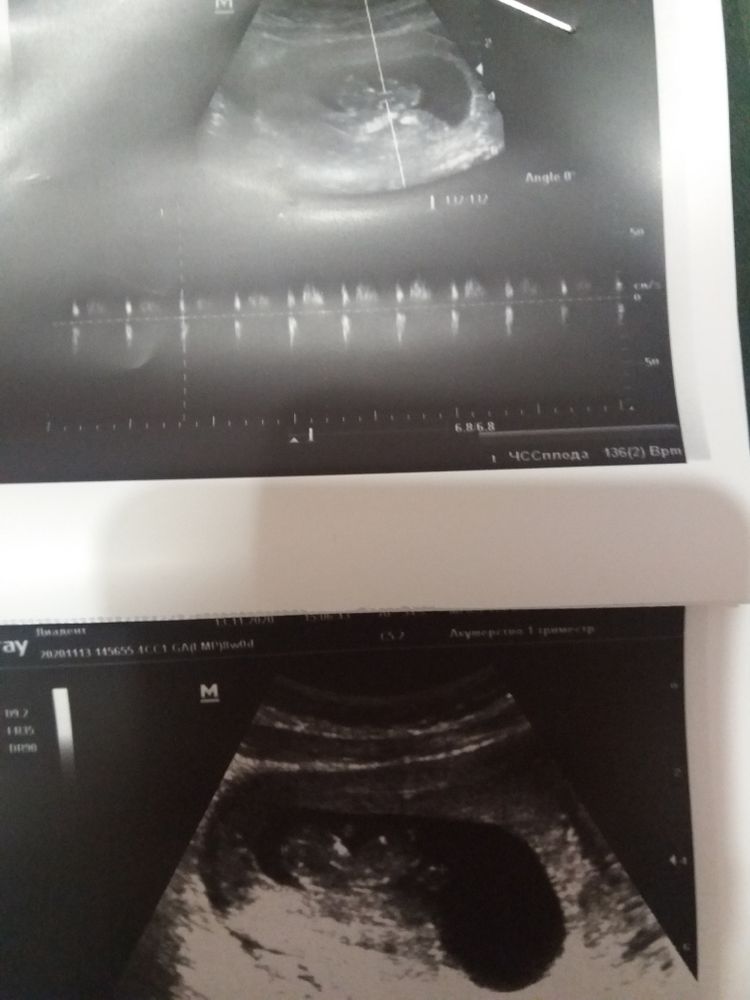

Карга в Зачатие 5 лет Пол ребенка Фолликулометрия Девочки, по методу Рамзи (если не перепутала) как вы думаете кто? Посмотрите еще 20 записей на эту тему Отменить Ответить Ирина По Рамзи смотрят 6-7 недель 😊 13.11.2020 Ответить Анна К По Рамзи актуально в 6-7 недель 13.11.2020 Ответить Карга ((( не знала. Я УЗИ то делала а это время, но у меня нет снимка, только замеры((( 13.11.2020 Ответить YanaM Срок больше 6-7 недель? 13.11.2020 Ответить Карга Yana, не. уюе ктр 35. 10 недель)) пальчики даже сегодня считали) 13.11.2020 Ответить YanaM Уже поздно для Рамзи) 13.11.2020 Ответить Карга Огооо. Блин((( а юя думала в любое время 13.11.2020 Ответить Карга А сердцебиение 138. Тоже вроде как-то определяют? Нет? 13.11.2020 Ответить YanaM Я думаю что ЧСС не показатель, но так вроде мальчик 13.11.2020 Ответить Карга Я чего-то залезла в нормы, мы не укладываемся по нормам в ЧСС по таблицам. Хотя узист сказала, что хорошее сердцебиение. 13.11.2020 Ответить YanaM Я считаю главным чтобы оно было. А количество актуально уже после 12 недель 13.11.2020 Ответить Карга После 12 недель это как раз вроде норма)) ну надеюсь все хорошо будет. 13.11.2020 Ответить Когда видно что была О по Узи Результаты УЗИ Чаты Беременных Выберите чат: Январята-2026 Февралята-2026 Мартята-2026 Апрелята-2026 Майчата-2026 Июнята-2026 Июлята-2026 Августята-2026